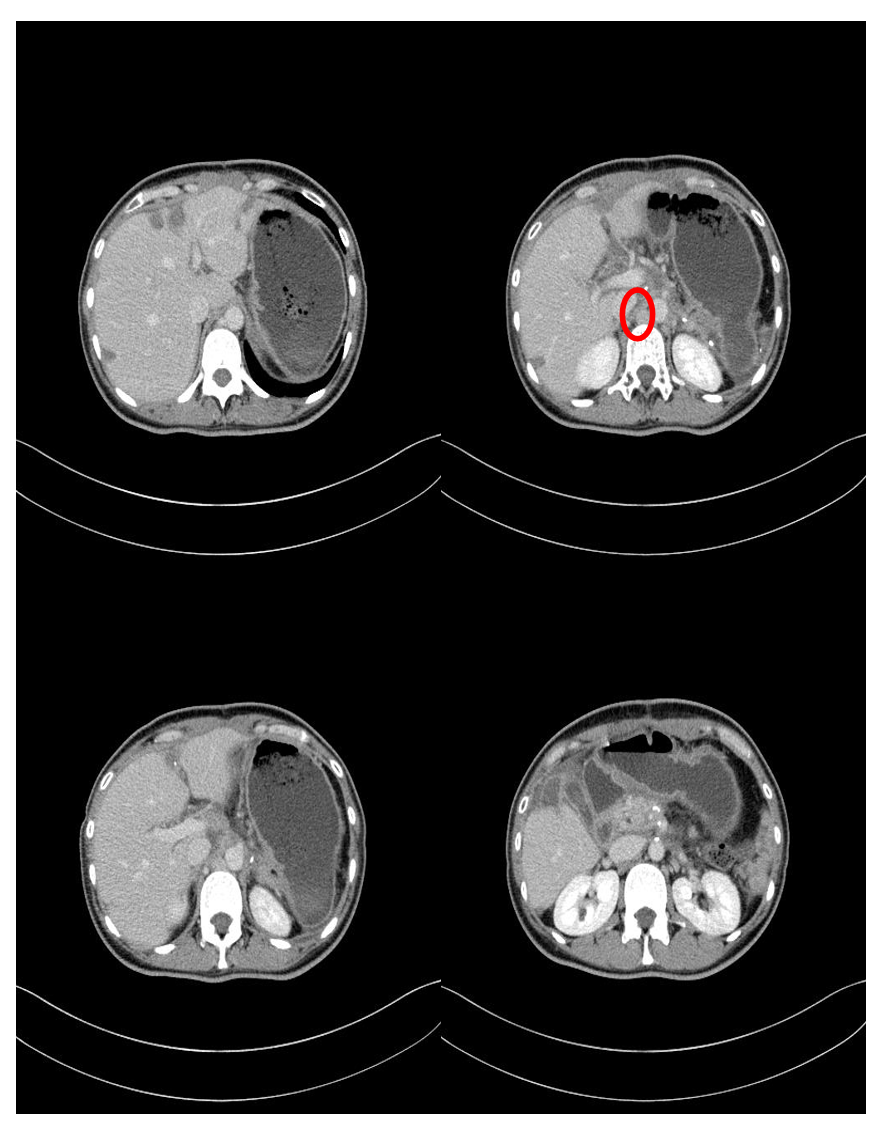

2023-12-22 CT检查示:胰腺尾部肿块,考虑胰腺癌:肿块接触脾动脉及胃体小弯侧,侵犯并堵塞脾静脉,周围侧枝循环形成,脾静脉内癌栓接近肠系膜静脉根部血管腔。胰腺肿块周围多发淋巴结转移瘤,肝脏多个转移瘤。2024-1-5我院超声造影:肝内多发实性稍高回声灶,考虑肝M可能性大。肿瘤标志物:CA19-9 (-)、CEA (-)、CA12-5 (-)。2024-1-30胸部、上腹部CT示:1. 胰尾部肿物、胰头结节,考虑胰腺恶性肿瘤可能性大,神经内分泌癌?2. 门脉主干、脾静脉充盈缺损,考虑癌栓可能。胰周数个淋巴结,考虑转移可能性大。肝内多发肿物、结节,考虑转移瘤可能性大。

CT复查疗效评价:胰尾部肿物、胰头结节,符合神经内分泌瘤,较前稍缩小。门脉主干、脾静脉充盈缺损,考虑癌栓,较前变化不大。胰周数个淋巴结,考虑转移可能性大,较前变化不大。肝内多发肿物、结节,考虑转移瘤,较前缩小。PET-CT复查示:胰尾部肿物葡萄糖代谢略活跃,生长抑素受体显像强阳性。胰头结节葡萄糖代谢未见明显异常,生长抑素受体显像阳性。胰周多发淋巴结葡萄糖代谢略活跃,生长抑素受体显像强阳性,考虑转移。肝脏多发病灶部分葡萄糖代谢略活跃,生长抑素受体显像强阳性,符合转移瘤。

基于患者胰头病灶仍存在,葡萄糖代谢未见明显异常,生长抑素受体显像阳性;68-Ga PET-CT显示胰头结节生长抑素受体显像阳性,于是患者接受术后长效生长抑素维持治疗。术后CT复查(2024-11)示:胰体尾部术后缺如,原术区积液、积气,积液较前减少。肝脏术后部分缺如,术区残腔形成,范围较前缩小。残肝内多发片状低密度灶,考虑消融术后改变。目前最新复查结果显示,患者整体病情稳定,仍处于“无明显进展’的状态。虽然胰头部仍可见一个小病灶,但该病灶自初次发现以来未见明显变化,形态稳定。患者目前正在规律接受长效生长抑素治疗。